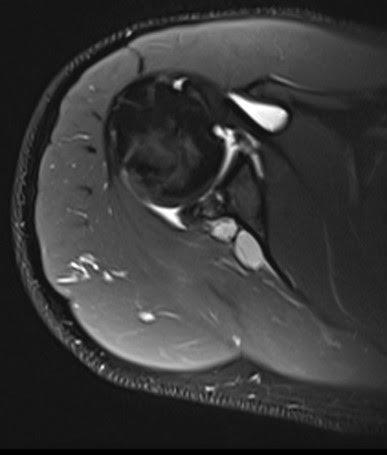

El vientre muscular del infraespinoso muestra incremento de señal miofibrilar, ligeramente mayor al estudio previo, lo cual sugiere cambios por denervación.

Se observa una rotura basal incompleta del labrum glenoideo tipo SLAP VIII, que se extiende de las 7 a las 3 en sentido horario, lo cual probablemente generó el quiste.

Subluxación posterior de la cabeza humeral con condrosis grado 4 y cuerpo libre osteocondral en el espacio subcoracoideo.